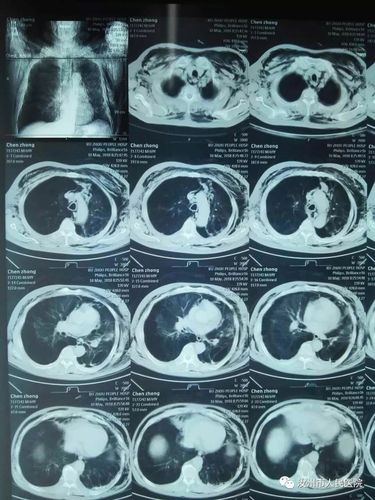

包裹性气胸or肺大泡这里有3个精彩病例

小切口解决大问题 胸腔镜下肺大泡切除